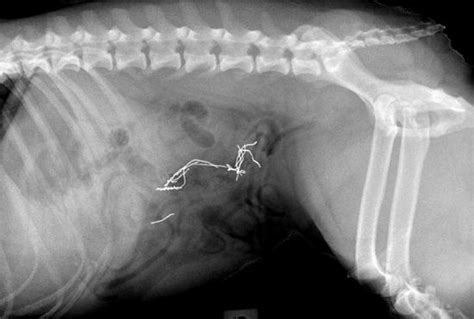

Do you want to know all about hairballs in cats? A hairball obstruction would eventually produce similar symptoms but not some of the damaging effects of 'foreign objects'. Symptoms of hairballs in cats. Normally, hair ingested by your cat passes through her intestinal tract and is expelled in the litter box. Hairballs can be normal for most cats, whether they have short or. Initially, vomiting is the only symptom that signals your cat has a hairball. Every cat owner knows about it: Hairballs, known to veterinarians as trichobezoars, occur as a result of cats grooming and swallowing the hair they remove.

In some cats, hairballs can become large and cause an obstruction in their gastrointestinal (gi) tract. How do i know if my cat has a hairball? You may notice your cat vomiting a particle that is the same color you may notice your cat is coughing up hairballs when you find vomit with pieces of hair, food, and fluid in it. As such, the kitty has to vomit them, cough them. The following are symptoms of an intestinal obstruction Sudden gi issues in a again, it could be an impassable hairball, but those symptoms can also signal other serious conditions. If your cat is having hairballs, you're not alone. It is normal for cats to vomit up the occasional trichobezoar, particularly longer haired cats. Sorry that this is really long. When a cat grooms, they will typically swallow hair. Cat hair gets tangled, mats, and sheds. In this new video from animalwised we explain how to avoid hairballs in cats, why a hairball can form. How to know if your cat is having a hairball.